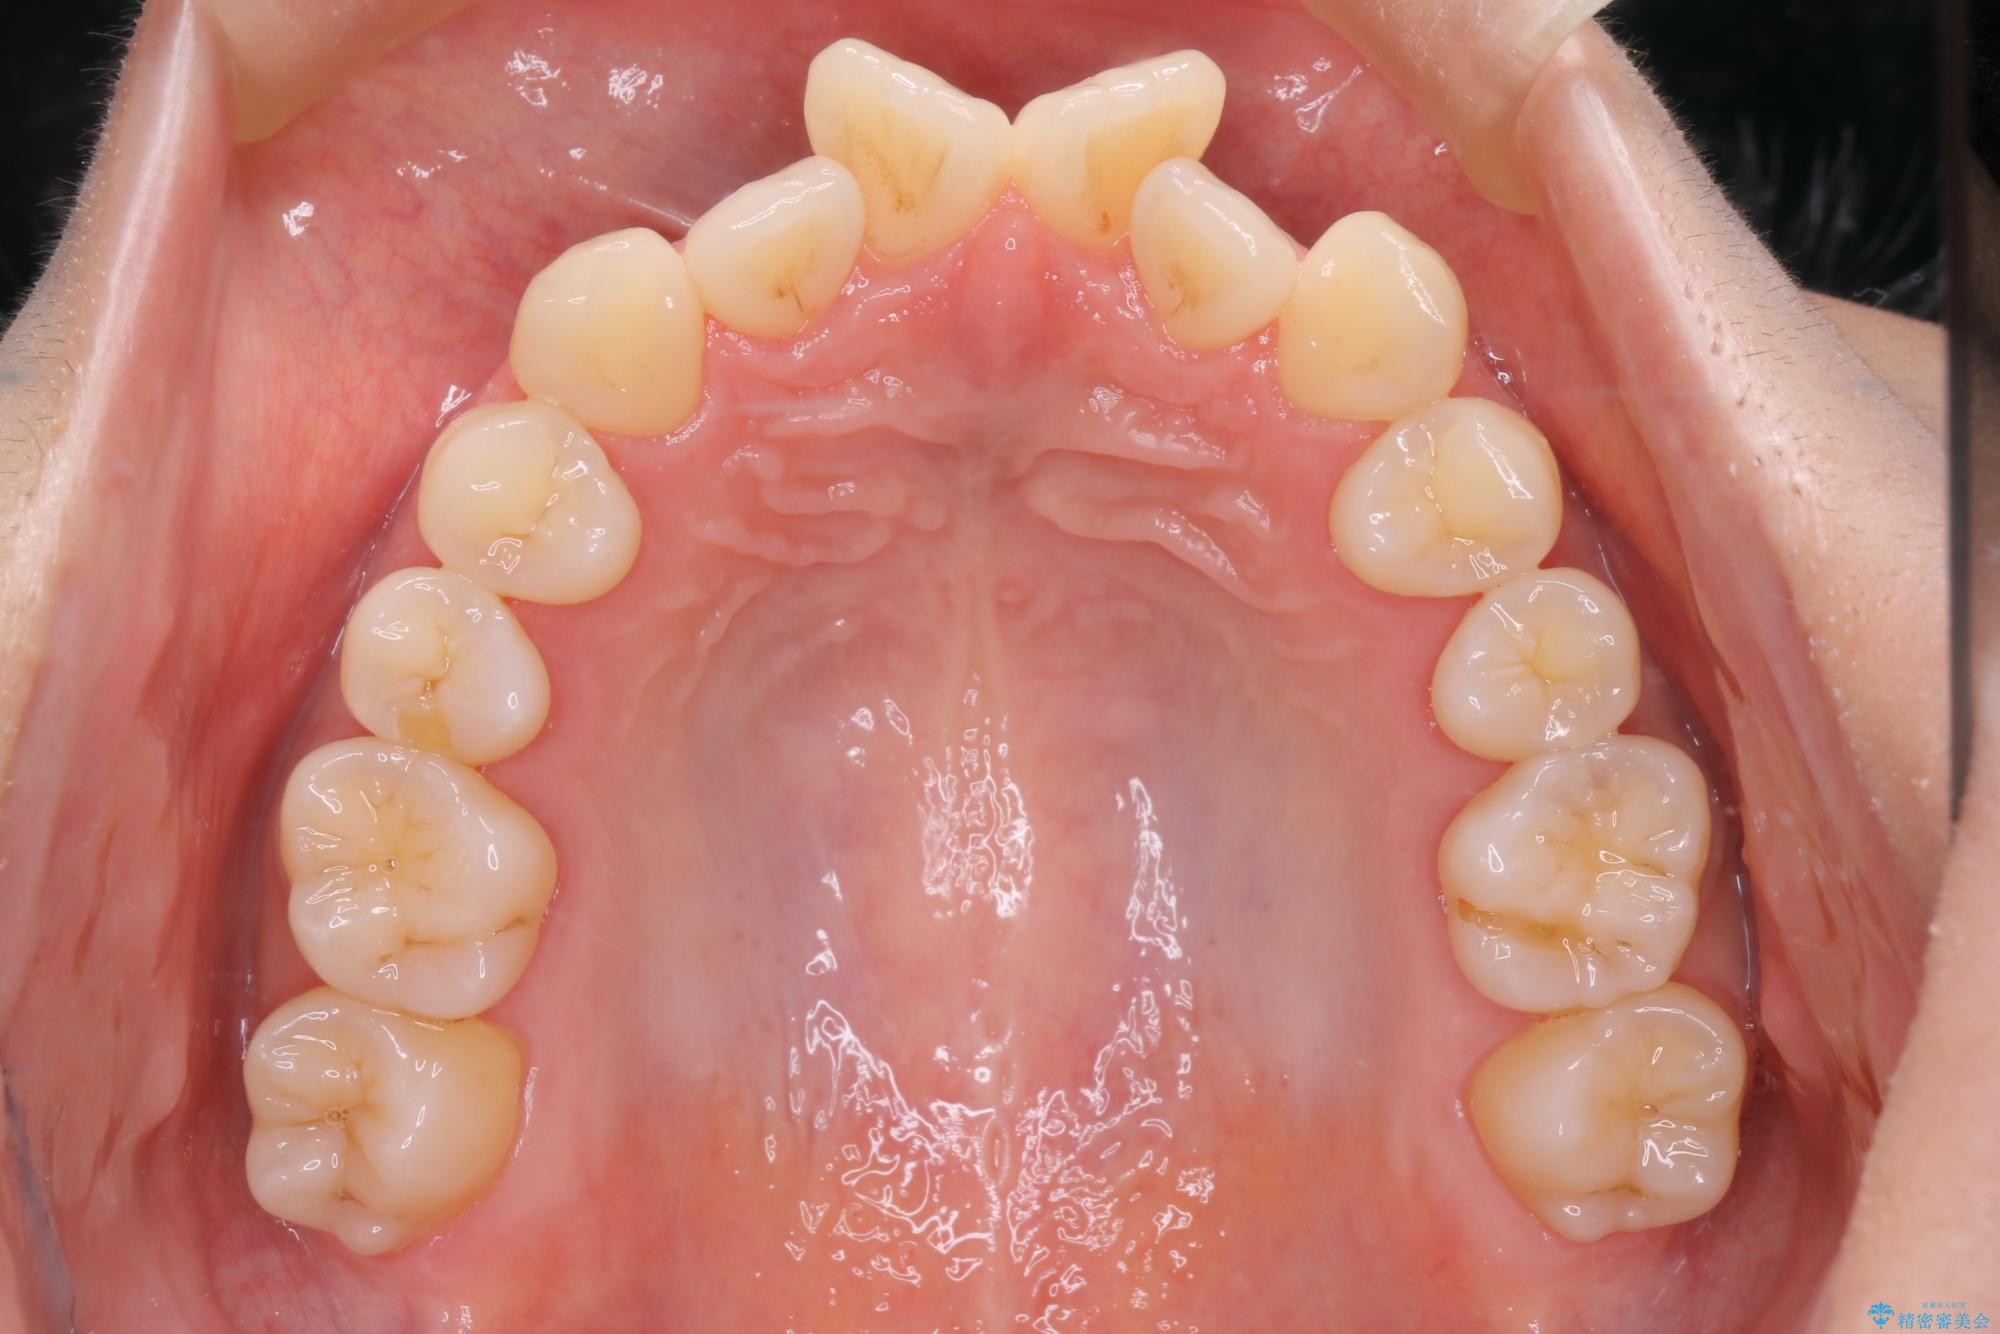

上の前歯のデコボコを主訴にご来院された患者様です。

重度の叢生が認められたため、上下左右4番目の歯を抜歯しワイヤー矯正治療を行いました。